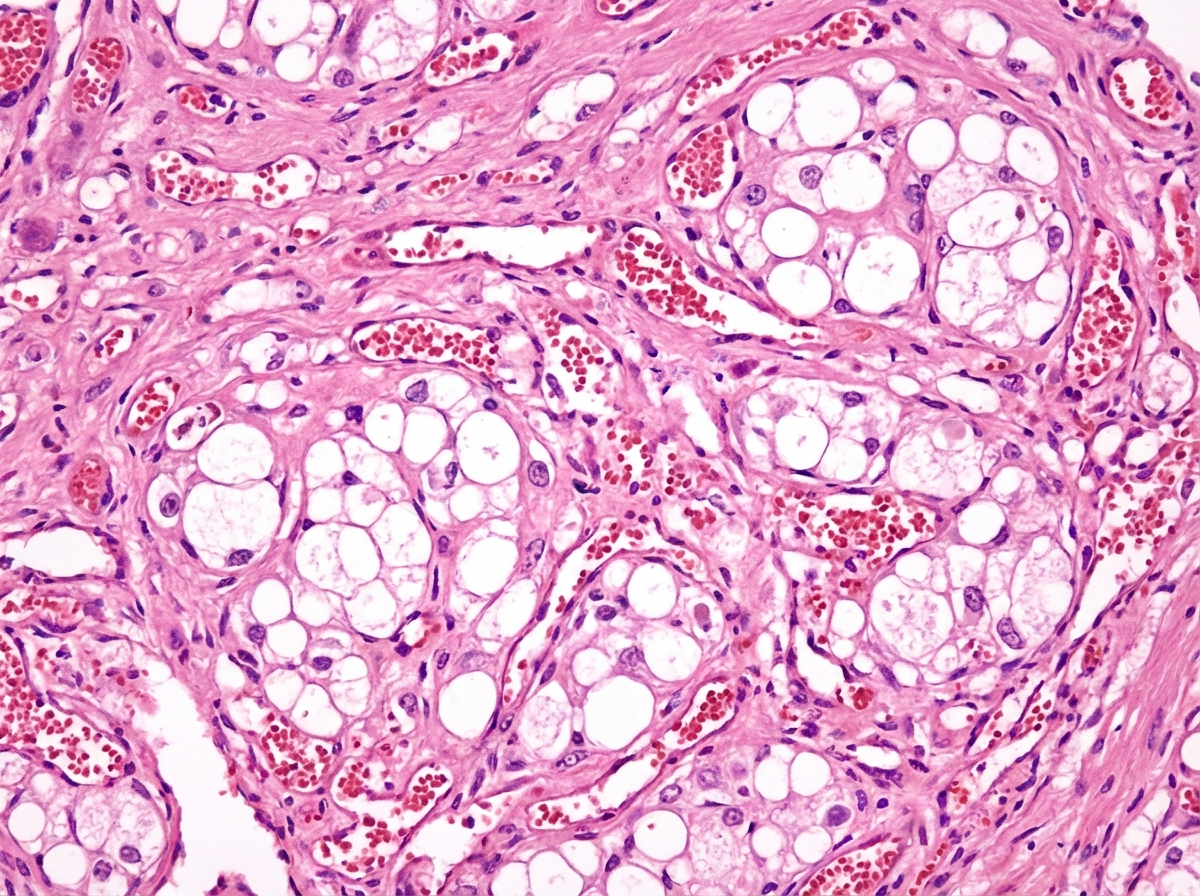

A 34-year-old patient with a history of anxiety, chronic constipation, chronic headaches, and chronic hypertension presents to the emergency room with severe right flank pain radiating to his scrotum. A urinalysis with stone analysis is performed and the results are shown in figure A. Prior to discharge, it is noted that the patients BP is still 170/110 mmHg. Furthermore, his calcium and PTH levels were both found to be increased. Which of the following representative histology slides of thyroid tissue represents a potential complication of the patients condition?